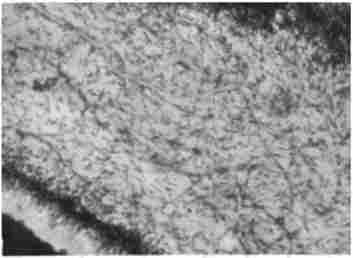

Пульпа зуба. Забарвлення гематоксиліном і еозином. Мікрофото, х 112,5

Мал. 1.1. Пульпа зуба. Забарвлення гематоксиліном і еозином. Мікрофото, х 112,5

Пульного зуба - це студенистой консистенції соединительнотканное утворення, що складається з основної речовини, клітинних елементів: фібробластів, нульпоцітов, сполучнотканинних волокон, шару одотобластов на периферії (рис. 1.1). Пульпа зуба розташована в замкнутій порожнині з непіддатливою стінками, має хороше кровопостачання, але колатеральний кровотік відсутній. Пульпа зуба має високу щільність нервових елементів, які займають 20,5% її обсягу. Нервовий пучок містить мієлінові А-дельта (28%) і безміеліновие С-волокна (72%).